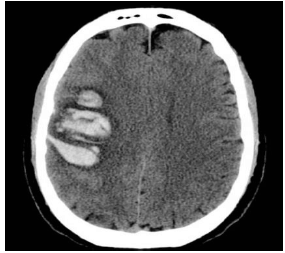

Paciente de 25 anos, do sexo feminino, usuária de anticoncepcional oral combinado, obesa, tabagista, sem outras comorbidades.

Internada na UTI com relato de cefaleia progressiva, em peso, com piora nas últimas 24h, agora bastante intensa e associada a náuseas e a vômitos.

Diante desse caso, foi realizada a tomografia de crânio que gerou a imagem a seguir.

A conduta adequada para essa doente é o(a)